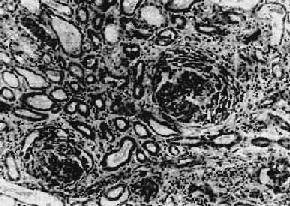

图12-11正常肾小球毛细血管及系膜增生性肾小球肾炎示意图

1.正常肾小球毛细血管及系膜示意图 2.系膜增生性肾小球肾炎示系膜增生

主要病变为肾小球系膜细胞和基质增生,系膜区增宽(图12-10,图12-11)。毛细血管壁无明显变化,管腔通畅。系膜内可有少数单核细胞和中性粒细胞浸润。病变严重者可引起系膜硬化。